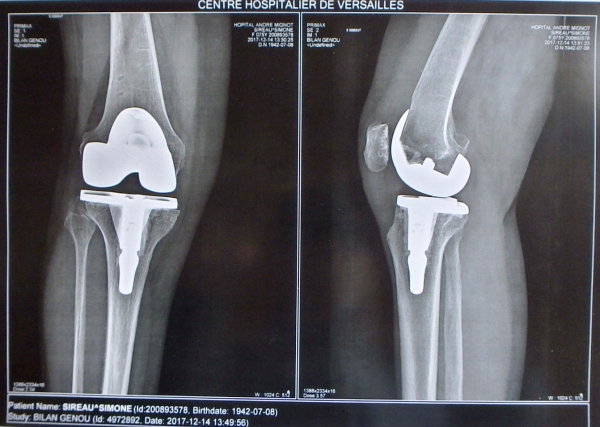

Radio des rotules après Prothèse Totale du genou droit de Simone (prise le 14 décembre 2017, 3 mois après l’opération).

Radio de la Prothèse Totale du Genou droit de Simone (radio prise le 14 décembre 2017, 3 mois après l’opération).